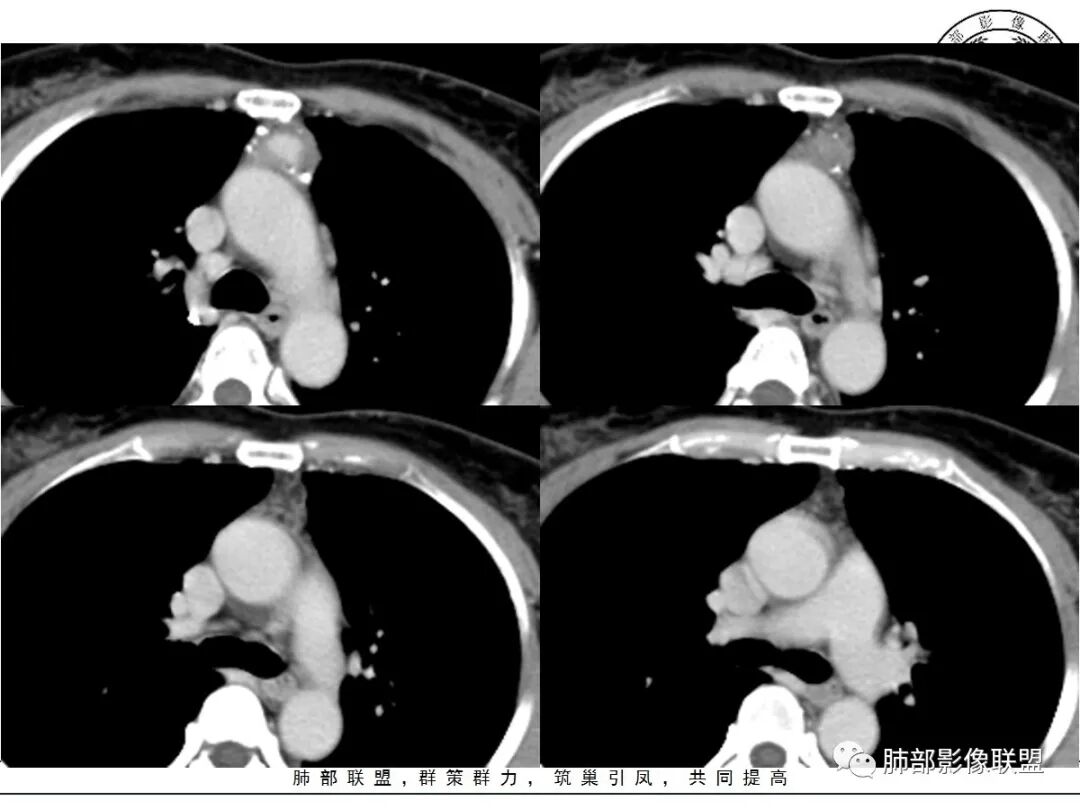

前纵隔海绵状血管瘤的影像学特征包括:①发生于前纵隔的圆形、类圆形、不规则肿块影,边界清晰,与邻近结构分界清晰;②CT上呈稍低密度影,内见小结节状、小片状、针尖状的钙化灶,钙化灶、静脉石影是海绵状血管瘤的特征性表现。③增强后大多数肿块可显示肿块的范围及供血情况,动脉期病灶边缘呈点片状强化,静脉期及延迟期逐步向内填充,呈渐进性强化等典型特征,部分不强化或轻度强化,部分增强 后片状强化,强化程度与邻近血管相仿;血管瘤强化方式与肿块内组织成分、血窦内血栓、血流等因素有关;Moran等研究表明,肿块强化不均匀或呈轻度强化的原因可能与扩张的血窦腔内组织平滑肌增殖及炎性纤维化有关;肿块血管样强化可提示海绵状血管瘤。前纵隔海绵状血管瘤需与畸胎瘤、胸腺瘤、胸内甲腺肿、神经内分泌肿瘤等进行鉴 别 断:①畸胎瘤多呈混杂密度影,内有脂肪、毛发、钙化灶及水样密度;②胸腺瘤呈结节状、团块状影,密度较均匀,增强后强化较均匀,与周围组织分界清晰;③胸内甲状腺肿位于前上纵隔,平扫密度常较高,可见其上端与颈部甲状腺相连;④神经内分泌肿瘤多伴坏死囊变,点片状钙化,形态常呈分叶状或 不规则形,增强后肿瘤实性部分强化显著。

综上所述,海绵状血管瘤发生在纵隔非常罕见,且缺乏典型的临床症状及特异性影像, 应从肿块的位 置、大小、形态、与周围组织的 关 系 以及CT平扫、增强特点进行分析,如前纵隔肿块内有钙化灶、静脉石、增强后点片状血管样强化及渐进性强化等特点,应考虑纵隔海绵状血管瘤的可能;薄层CT及其多平面重组有利于发现细小钙化灶,而动态增强CT扫描能更好显示肿块内血管强化,有助于术前诊断与鉴别诊断。